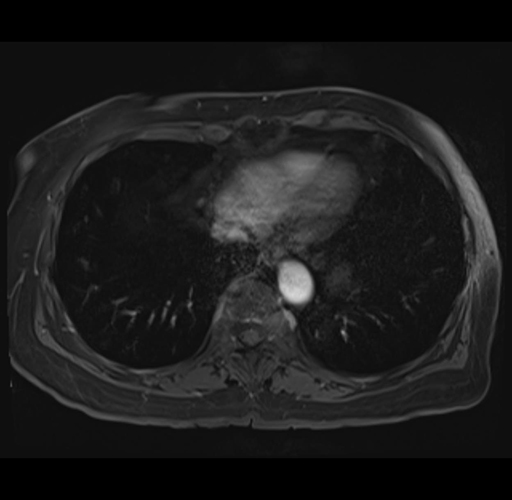

MRI T1

Imaging analysis